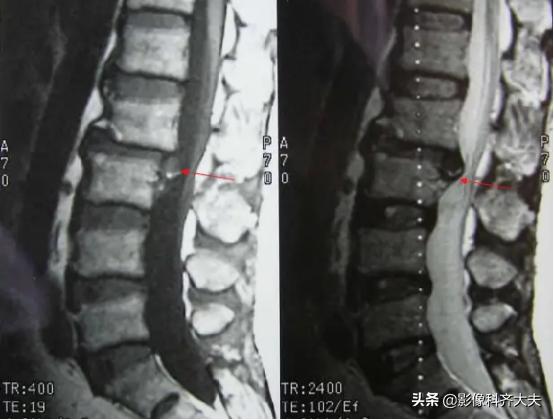

磁共振显示椎间盘脱出